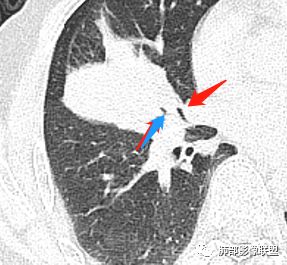

主病灶在中叶,但是左肺舌段叶有条索影,陈旧病变。蓝色箭头支气管受压,是淋巴结肿大

主病灶在中叶,但是还有结节状病变在下叶

这个支气管是走形通畅,但是壁增厚的。比较符合炎症改变

内侧段是通畅但是受压的

外侧段一开始狭窄

但是远端通畅,所以我认为支气管都没有堵塞,不太可能是鳞癌

支气管进入其中,远端粘液栓

墨西哥仙人掌征---结核        影像上结核灶,粗大的均匀枝干,推测是支气管囊状扩张引起的,在非支气管区,形成圆形坏死囊群;如果这些坏死比较稀薄,又遇到扩张支气管,就会形成粗大的“墨西哥仙人掌”。结核引起的支气管近端炎症纤维化,可以造成支气管阻塞,从而将干酪样坏死物封堵在管腔内。仙人掌主干内部应该是干酪为主,稀薄的,具有流动性,时间久了会出现钙化。